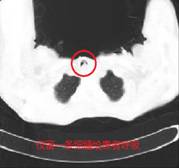

胸部CT及之后支气管镜检查证实了气管内塞满了一粒粒葡萄大小的肿瘤。而且肿瘤向下长到气管胸骨入口以下,即使行气管插管也没有用,如果不积极处理,患者会被活活憋死。